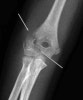

X-ray : 외과 골절(Lateral condyle fracture)